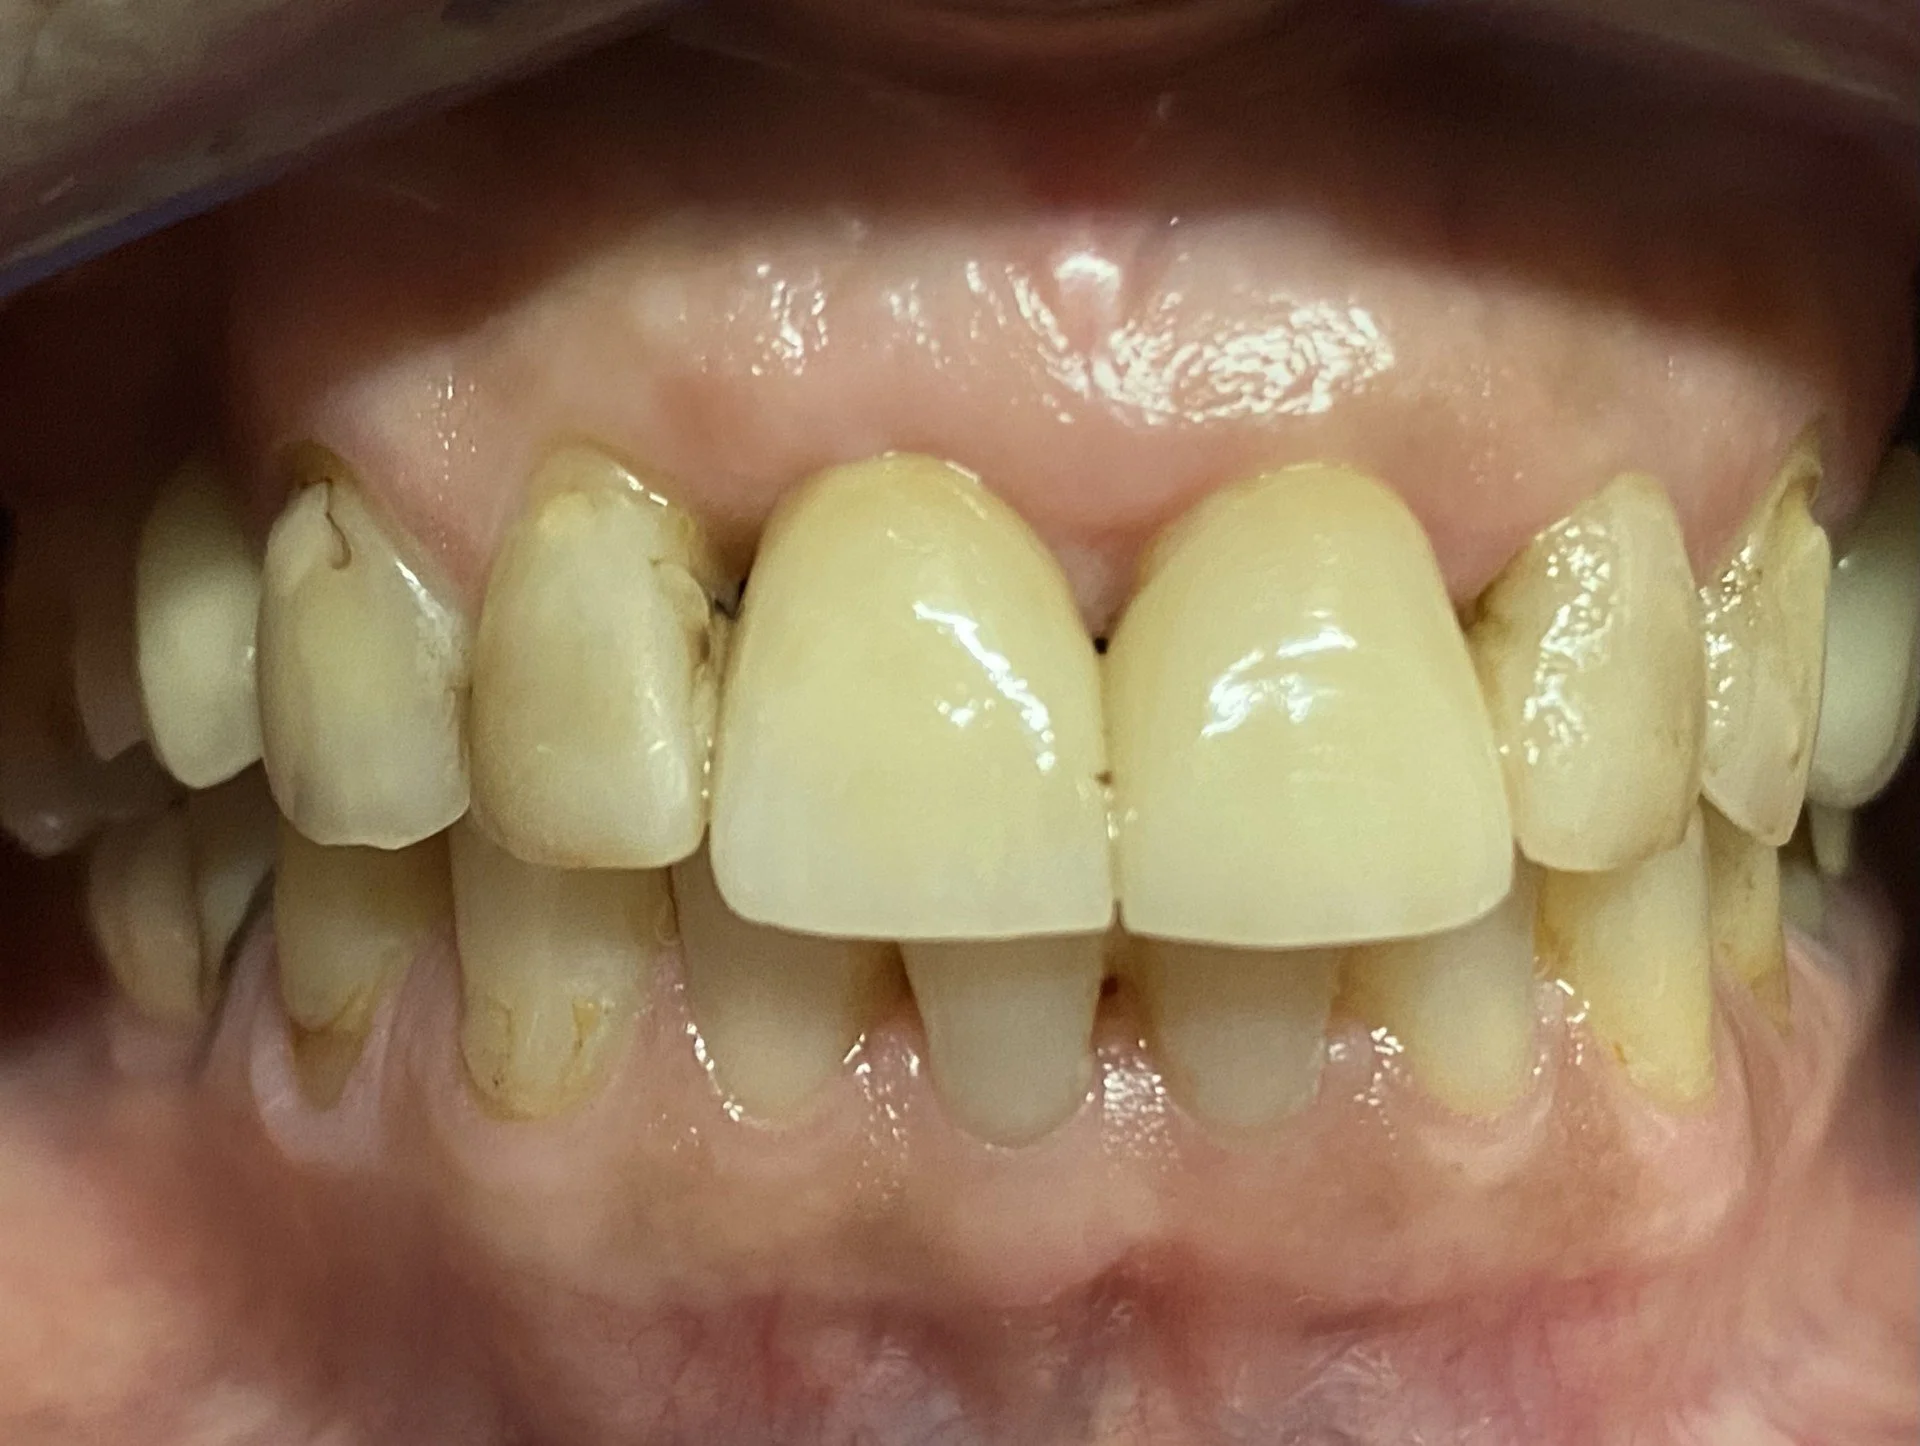

This 65 year old patient had numerous dental problems including decay, periodontal gum disease involving moderate to concerning future bone loss, missing teeth, heavily filled teeth and an extremely difficult very deep overbite.

Part of the deep overbite and a heavily discoloured top left number 2 lateral incisor previously extracted, root sectioned and amalgam filled prior to reattaching as a bonded bridge tooth to the adjacent top left number 3 canine tooth.